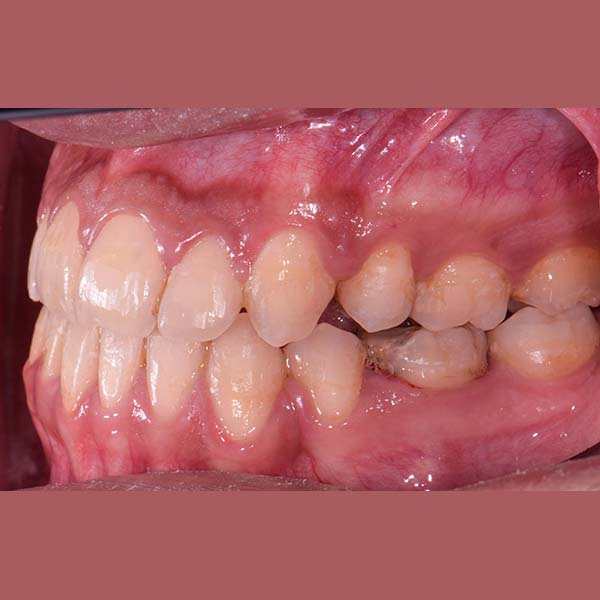

BEFORE

My young friend visited me suffering from a complete Bite collapse, a severe anterior crossbite, in addition to the loss of many of his back teeth. He was so frustrated, thinking that his case is incurable, and this frustration was reflected on his shy smile.